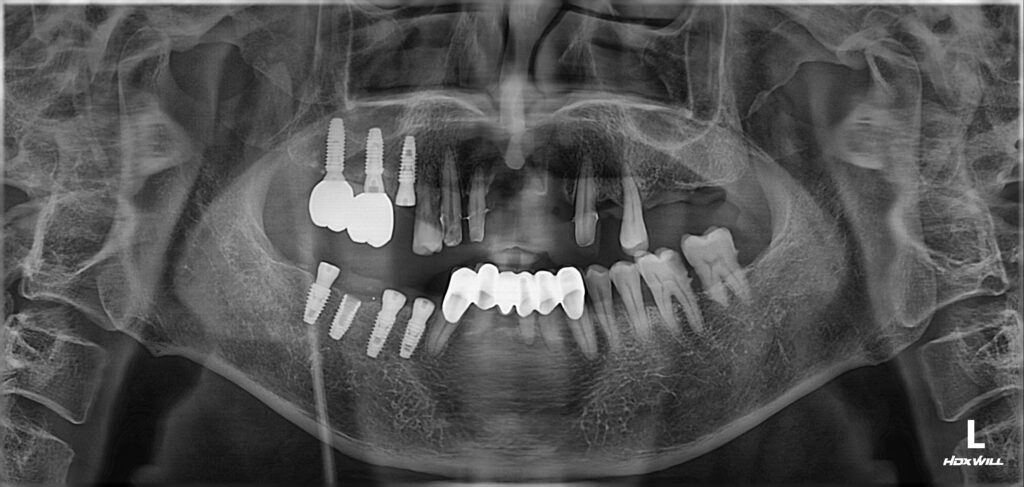

어금니 치료와 동시에 앞니 치료를 권장 드렸으나 환자분께서는 우측 어금니를 먼저 완성하고 싶다고 하셨네요.

오른쪽 위아래 임플란트 식립한 뒤 임플란트와 뼈가 단단하게 붙는 기간인 2개월여 기간 동안 염증이 생긴 앞니는 발치한 뒤 브릿지로 된 임시치아를 사용하셨습니다.

임플란트 수술 후 2개월이 지난 시점에서 임플란트와 뼈가 얼마나 잘 붙었는지 확인 후 본을 떠서 보철까지 진행이 되었습니다.